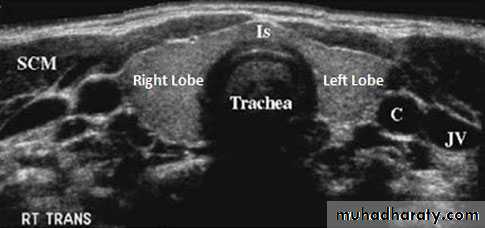

24Us of thyroid gland and neck

Tuesday, November 04, 2014